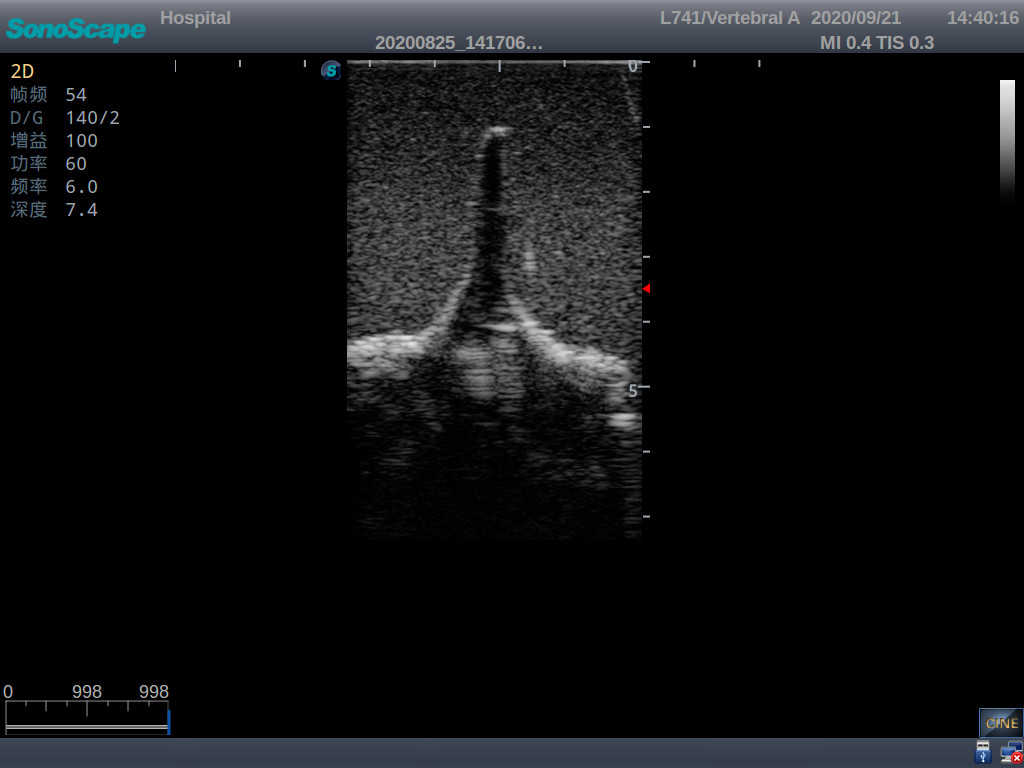

Model TYE1549.2

This model is an ideal choice for ultrasound-guided adult lumbar puncture training with true-to-life skin feel and touch, accurate anatomical structures as well as real clinical ultrasound images. Realistic resistance to needle tips and correct landmarks provide excellent hands-on experience.

· Realism:

1)  Advanced material for true-to-life skin touch, feel and puncture

2)  Real clinical ultrasound images

3)  Compatible with various real ultrasound machines